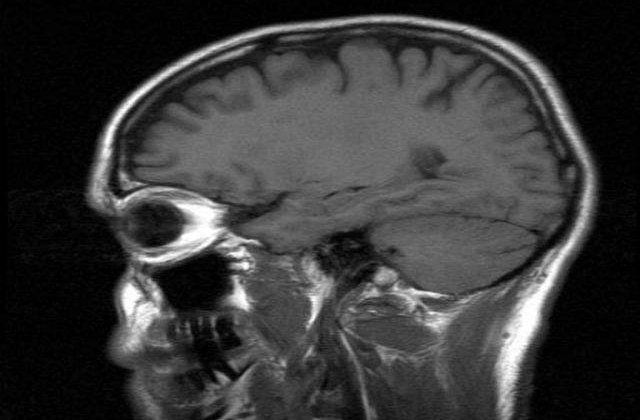

Potrivit unui studiu facut de oamenii de stiinta olandezi exista anumite lucruri extrem de banale care maresc riscul declansarii hemoragiilor cerebrale (care se petrec atunci cand un vas de sange slabit, la nivel cerebral, se sparge). Iata cativa dintre acesti factori care cresc tensiunea arteriala - principala cauza a spargerii capilalelor cerebrale.